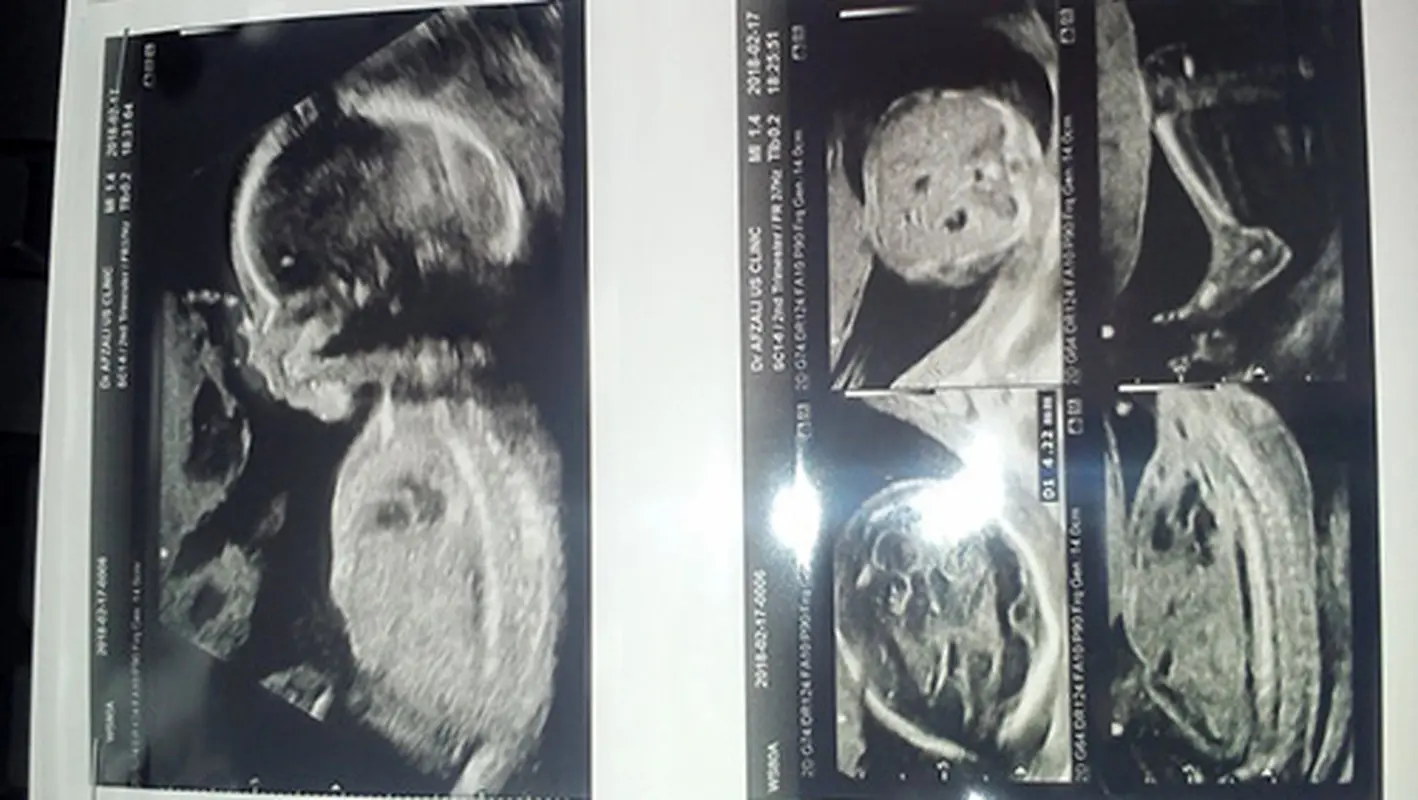

سوال مخاطب نینیبان: من ۲۶ ساله دربارداری دوم هستم در سونو انومالی من دکتر گفت :

در هفته 21 بارداری یک مامبران نازک در لبه تحتانی جفت قدامی مشاهده میشود وبقیه پوزیشن ها نرمال است. وباید هر ماه سونو بشی تا این باند فشاری بر جنین نداشته باشد. این باند برای جنین چه میزان خطر دارد؟

پاسخ دکتر مرجان قاجار، جراح و متخصص زنان، زایمان و نازایی:

صرف یک گزارش نمیتوان نظر داد.سونو را تکرار کنید. اگر واقعا محل باند روی جفت باشد مشکلی ندارد اما اگر روی جنین باشد میتواند اثر فشاری بر جنین داشته باشد.تنها راه برآورد میزان خطر هم تکرار و پیگیری با سونو میباشد.